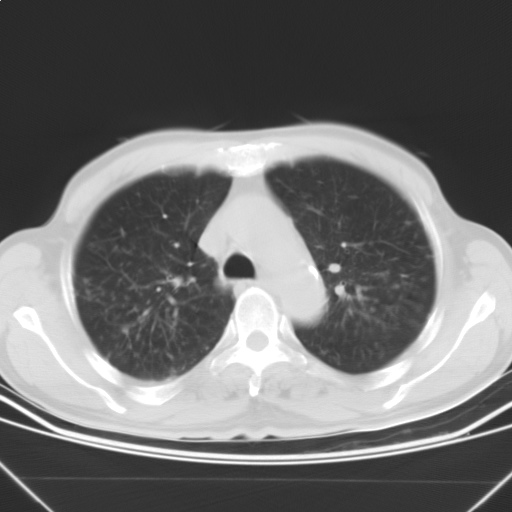

以下是引用随光逐影在2009-5-1 13:53:00的发言:[br]考虑为:1)两肺血行播散型肺结核;2)右肺下叶炎症感染。3)右侧胸膜增厚。